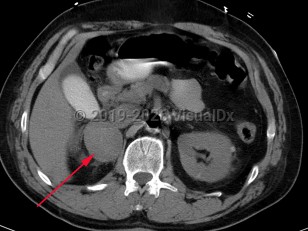

Pheochromocytoma

Pheochromocytoma (PCC) is a rare catecholamine-secreting neoplasm of adrenal origin; when it is extra-adrenal, it is referred to as paraganglioma. PCC is known as the "great masquerader" because of its similarity in clinical presentation to many other conditions. Up to 15% of patients may be asymptomatic. The most common presenting symptoms are hypertension (including labile hypertension), palpitations, increased sweating, severe headache, tremors, pallor, and dyspnea. Atypical symptoms include anxiety, abdominal pain, nausea, vomiting, constipation, insomnia, and weight loss. The prevalence of PCC in patients with hypertension is less than 0.2%. Rarely, paragangliomas may occur in the heart. Cardiovascular complications of catecholamine excess are rare but can lead to stress cardiomyopathy. Clinical presentation is characterized by transient duration of symptoms (eg, 15-20 minutes) that may recur several times a day. Physical exertion (moderate to extreme exercise) or bowel movements may provoke symptoms. Sometimes a pheochromocytoma is found incidentally during a workup.

The majority of PCCs are intra-adrenal and solitary. Approximately 10% of all catecholamine-secreting tumors will be malignant. PCC may occur at any age but has the highest prevalence in individuals aged 20-50 years.